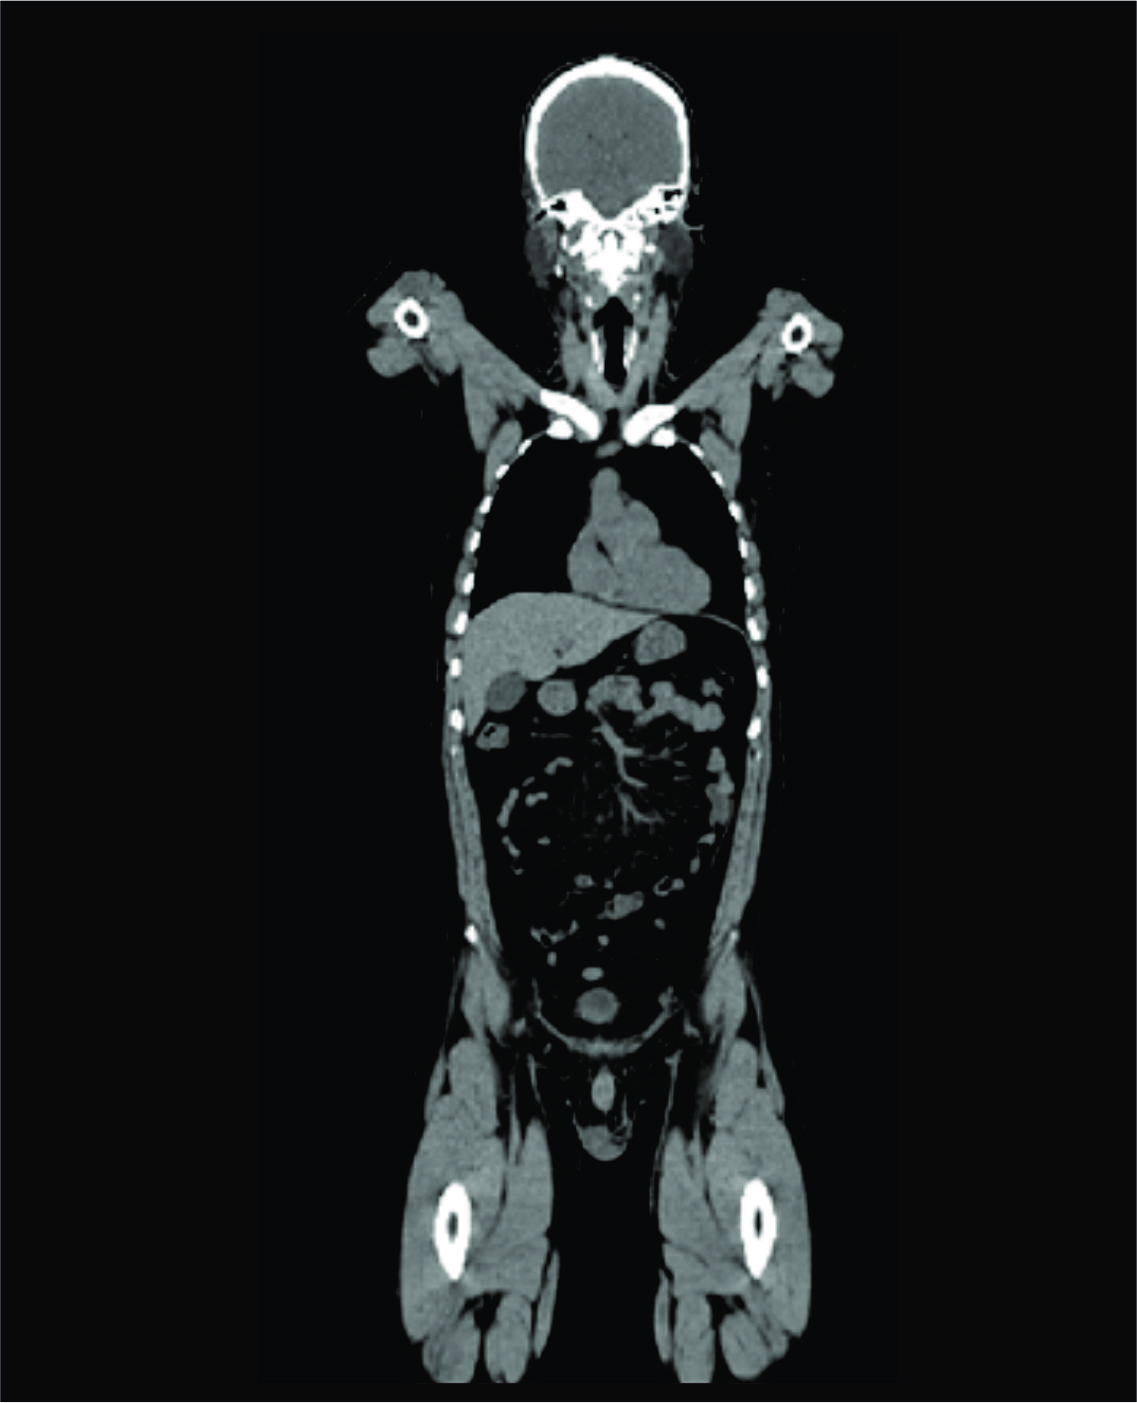

O exame de tomografia é rápido e geralmente leva apenas alguns minutos para ser concluído. Você precisará ficar imóvel durante a aquisição das imagens para garantir que elas saiam nítidas e precisas. Em média, o procedimento dura de 10 a 30 minutos, dependendo da área do corpo que está sendo examinada.